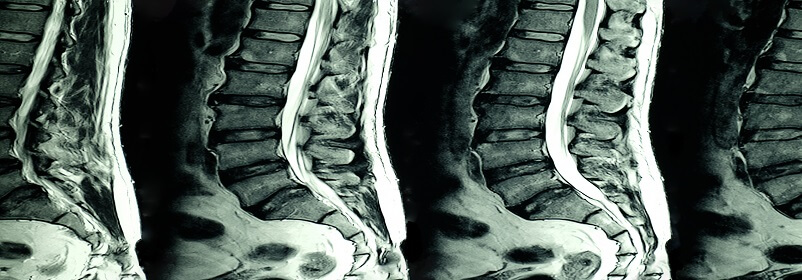

سعر الاشعه الرنين على الظهر، تعتبر تقنية الاشعه الرنين على الظهر من أبرز التطورات التكنولوجية في مجال الطب، حيث تستخدم لتقديم تشخيص دقيق لعدد من الحالات الطبية، حيث تعتمد هذه التقنية على استخدام المجال المغناطيسي والموجات الراديوية لإنشاء صور تفصيلية للأعضاء الداخلية في الجسم.

هو تقنية غير جراحية يتم إجرائها بواسطة المجال المغناطيسي والموجات الراديوية بدون الحاجة إلى الإشعاع، بهدف الحصول على صور دقيقة ثلاثية الأبعاد لأجزاء الجسم الداخلية، وذلك من خلال توظيف موجات الراديو وجهاز كمبيوتر متطور.

وتعتبر هذه التقنية أداة فعالة في الكشف عن الأمراض وتشخيصها بالإضافة إلى متابعة مدى فعالية الخطة العلاجية، حيث تعطي هذه الاشعه تصوير دقيق حول العمود الفقري القطني شامل العظام والأقراص والحبل الشوكي والتركيبات الأخرى في أسفل الظهر.